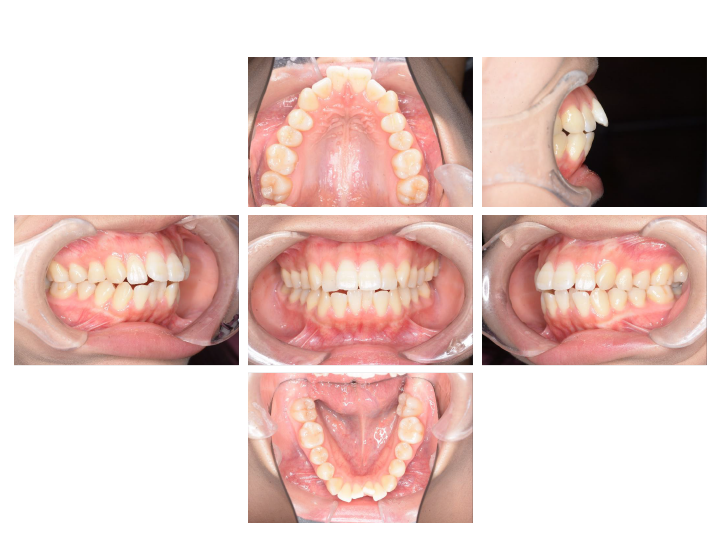

お子さんの矯正(小児矯正)は、あごの骨のバランスや大きさを整える「1期治療(骨格矯正)」と、永久歯が生えそろってから歯の位置を整える「2期治療(歯列矯正)」の2段階からなります。

乳歯と永久歯が混じった時期の治療で、主に成長を利用した治療を行ないます。(6~10歳)

歯の1本1本に装置をつけ、歯の根までコントロールして最終的な咬み合わせを作ります。